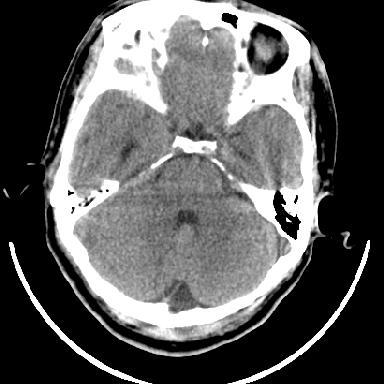

标题: CT6056:脑出血(血管畸形?) [打印本页]

标题: CT6056:脑出血(血管畸形?)

m 40突发头痛左侧偏瘫3小时

另附部分资料:“血液溢出血管外形成血肿,其内含有大量血红蛋白、血浆白蛋白,球蛋白,因这些蛋白对x线的吸收系数高于脑质,故ct呈现高密度阴影,ct值达40~90h,最初高密度灶呈非均匀一致性,中心密度更高,新鲜出血灶边缘不清。基底节区血肿多为“肾”型,内侧凹陷,外侧膨隆,因外侧裂阻力较小,故向外凸,其它部位血肿多呈尖圆形或不规则形”

术中抽出40ml陈旧血液,血肿底部似见一条索血管影